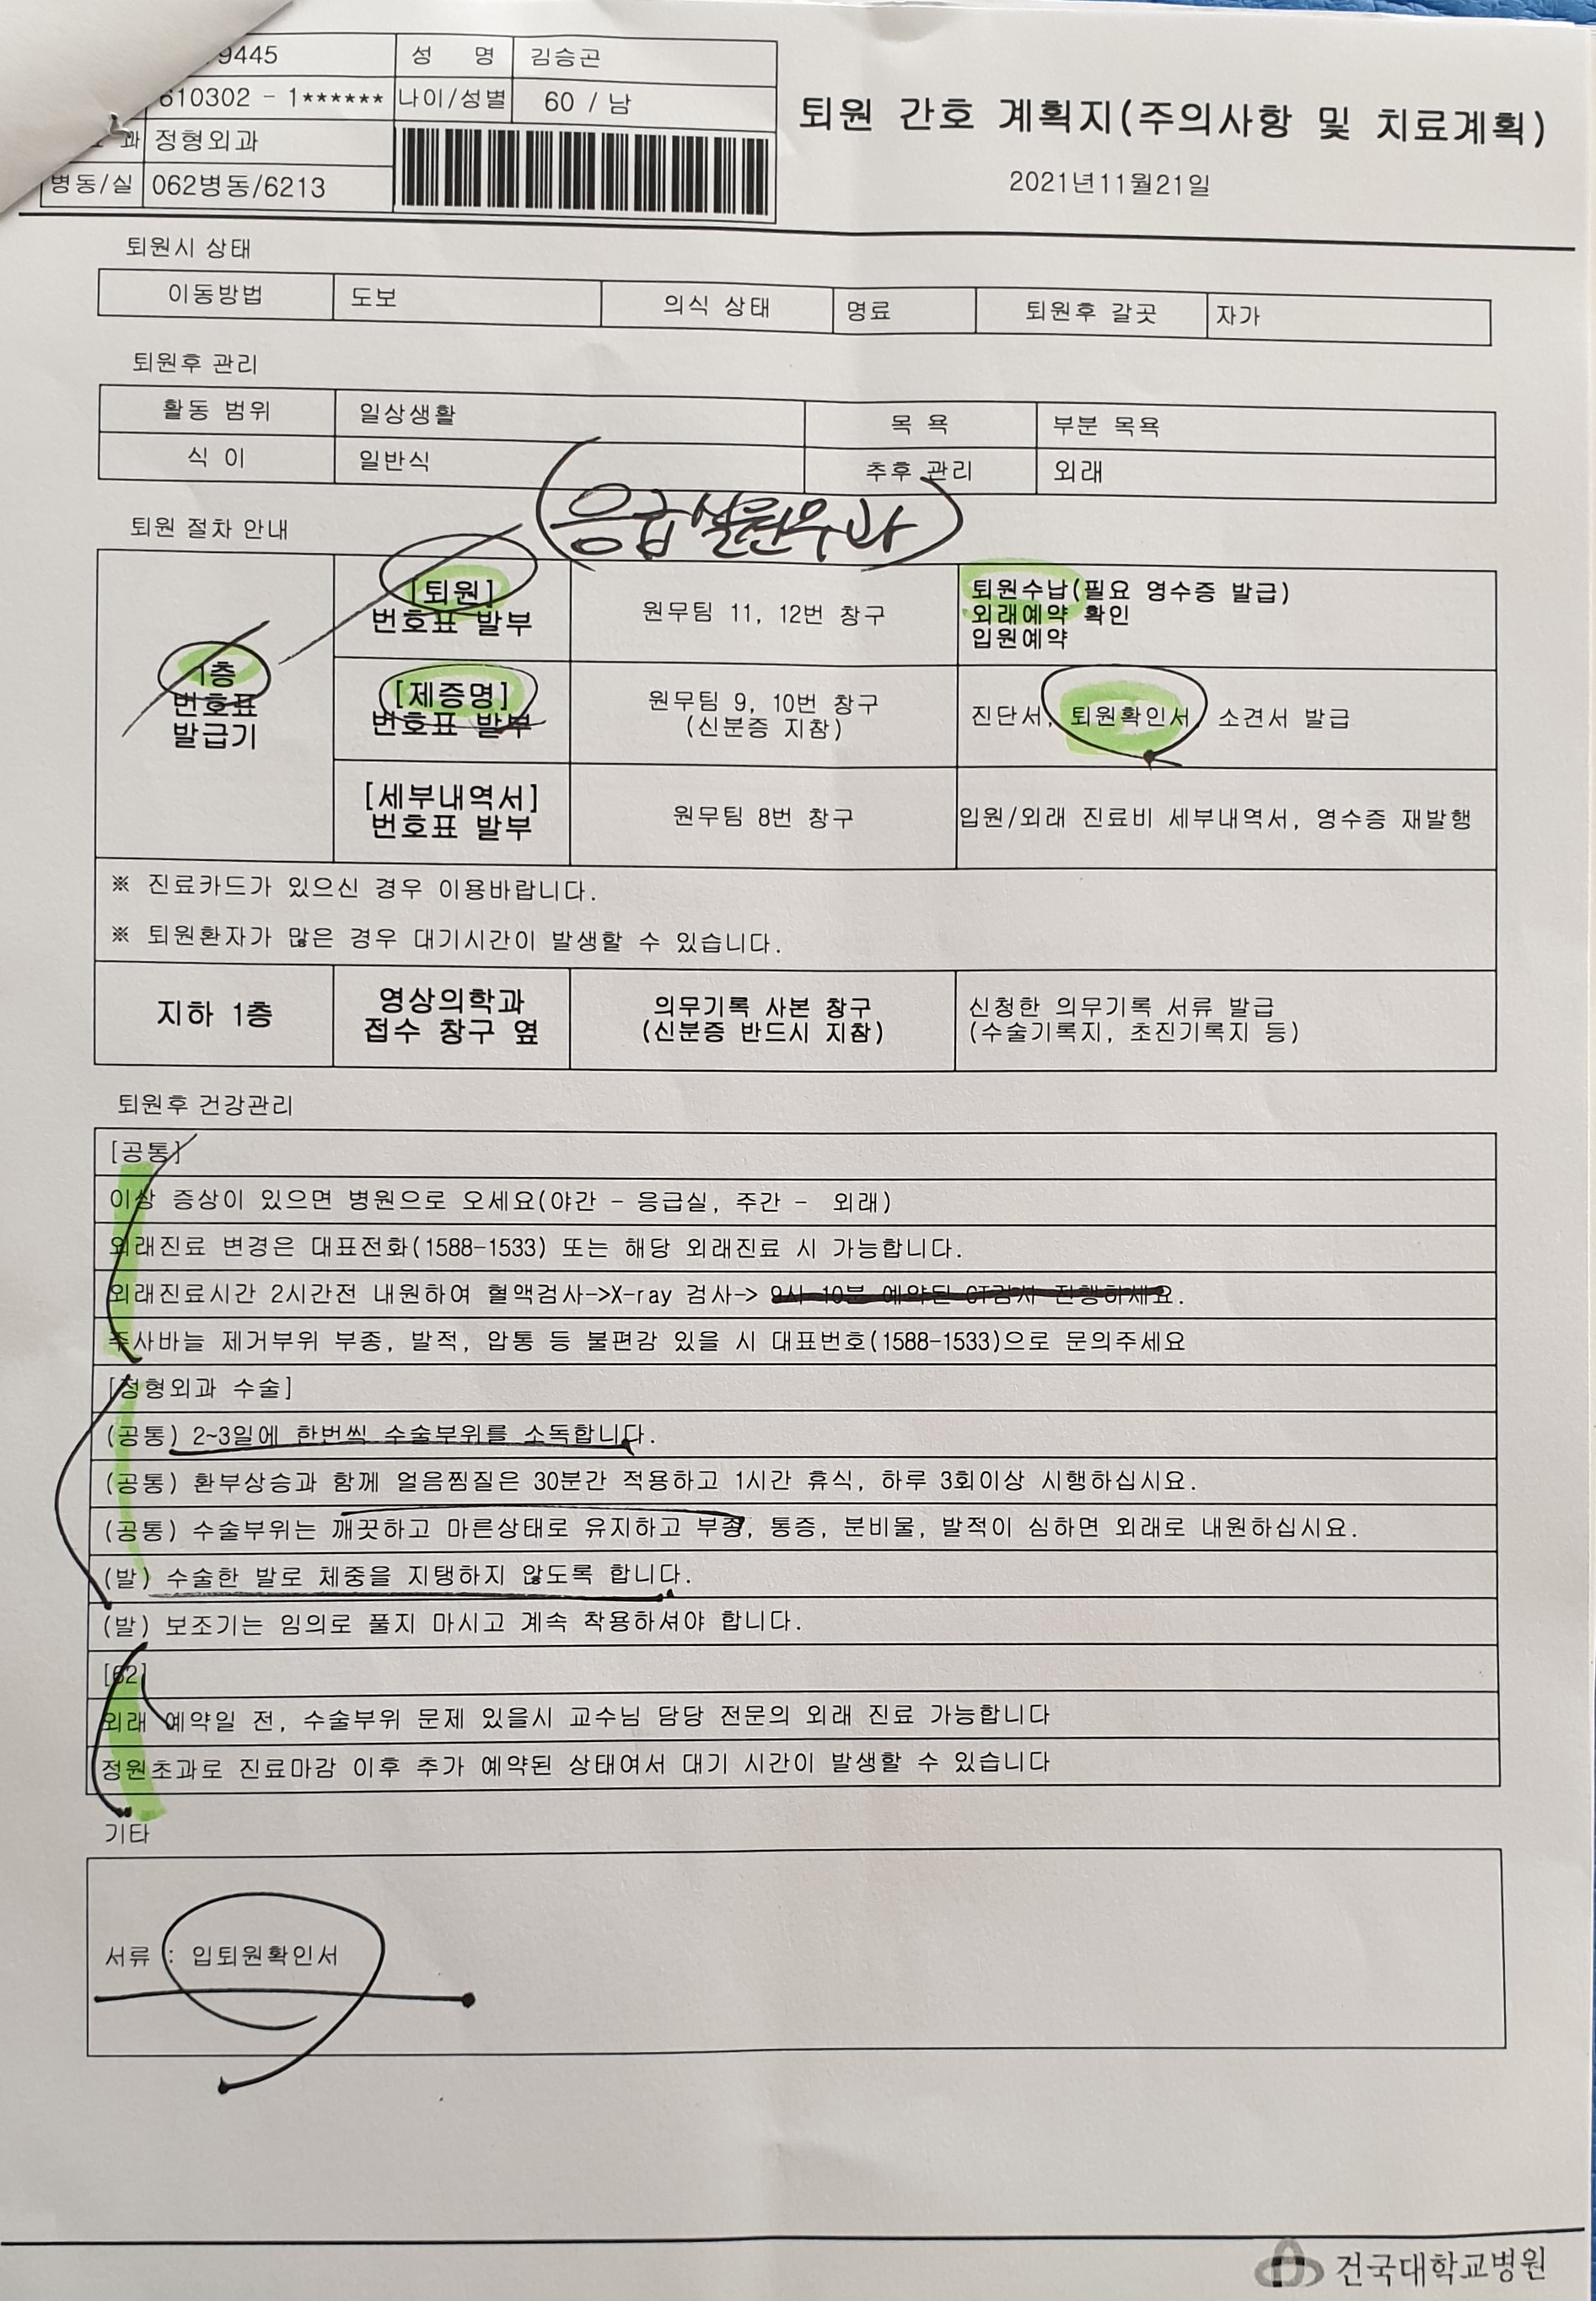

일정을 논의하는데 12월 15일 입원해서 16일 수술 하는걸로

그리고 다음 진료일을 11월 22일로 잡았는데 그날 MRI 를 다시 찍고 수술전 검사를 하는걸로 했다.

그리고 지방가서 상처주위 소독을 잘해라, 또 일요일쯤 퇴원 해도 돤다 뭐 그런 이야기이다.

VACO ped

정형외과에서 발목을 치료를 한다.

퇴원 치료라고....

그리고 수술할때 차고 있던 가부스를 벗겨버리고 VACO ped를 신겨준다.

비싼거라며

그리고 나중에 다 낳거던 중고시장에 팔아라는 귀뚬까지 한다.

빠르면 09시 30분일거라는 퇴원 소식이 10시쯤 왔다.

가퇴원이란다.

320만원.............

아내가 올라오더만은 명의값 한다는 이야기다.

생각보다 많이 나온게사실이다.

검사비 진료비 포함하면 500만원은 족히 날아갈듯한 치료비이다.

어째튼 카드 결제후 다음주 진료하는날 와서 정산을 받으라는 이야기이다.